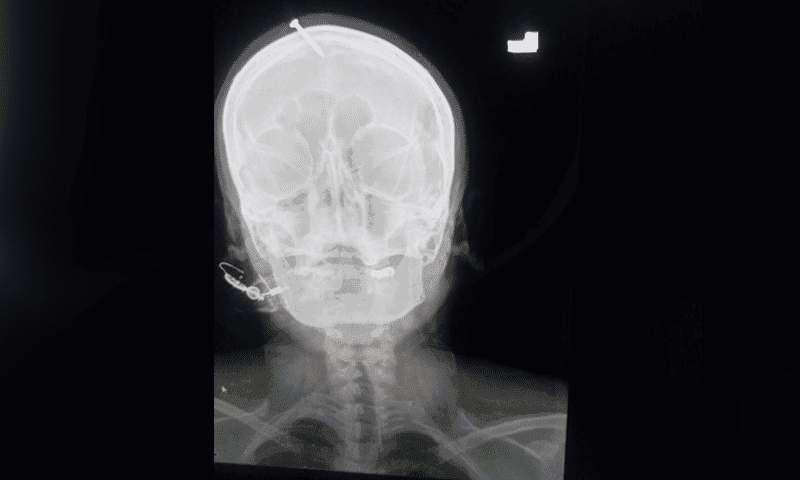

وطن – كشف موقع “dawn” تفاصيل واقعة صادمة ومأساوية في الهند لسيدة دُق مسمار في رأسها. بواسطة دجال أملا في أن تلد صبيا بعد ولادتها لثلاث بنات حيث كانت تخشى أن يطلقها زوجها.

ووفق ترجمة (وطن) فقد تابعت شرطة الحادث في مدينة “بيشاور” بعد أن ظهرت امرأة في المستشفى وقد دُق مسمار في رأسها. على ما يُزعم بتوجيهات من معالج ديني من أجل ولادة صبي.

من جانبه قال الدكتور حيدر سليمان، جراح الأعصاب المقيم في المستشفى. إن الضحية كانت تنزف عندما تم إحضارها وتم إعطاؤها الإسعافات الأولية قبل نقلها إلى غرفة العمليات.

اخترق الجمجمة بعمق

وتابع: “ذكرت الضحية أن امرأة في منطقتها فعلت الشيء نفسه ودقّت مسماراً في رأسها وأنجبت طفلاً. على الرغم من أن الموجات فوق الصوتية أظهرت أن طفلها الذي لم يولد بعد هو بنت”.

وقال الدكتور سليمان إن المسمار اخترق جمجمة الضحية بعمق.

وتابع أن أسرتها ذكرت أنها كانت في المنزل وفقدت الوعي. مشيرًا إلى أنه جرت محاولات أيضًا لإزالة المسمار من رأس المريضة في منزلها.

وقال “لقد حاولوا إزالته في المنزل لكنهم لم يستطيعوا ذلك”. مضيفًا أن الأطباء نجحوا في إزالته بعد إجراء عملية جراحية لها.